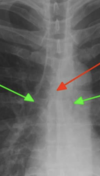

ECG changes of an MI?

ECG changes MI [within 12 hours] 1. ST elevation in more than one consecutive leads 2. Elevation: more 2mm chest leads, more than 1mm in limb leads